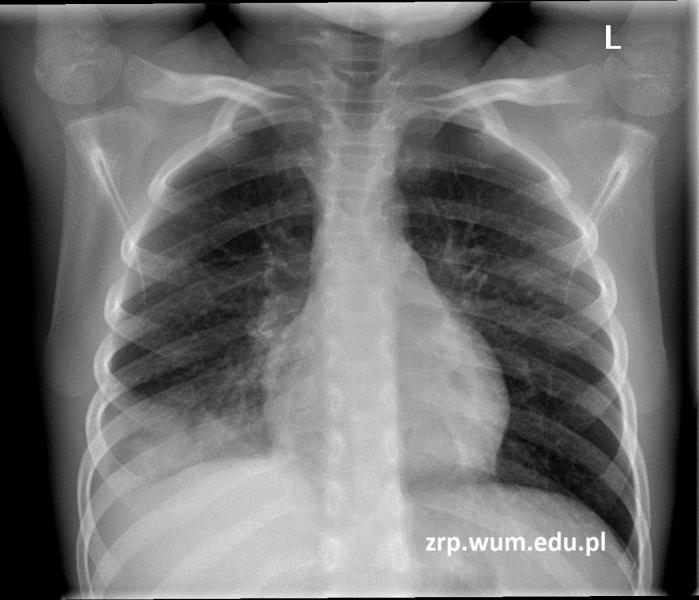

8-letnia dziewczynka z gorączką i klinicznym podejrzeniem zapalenia płuc

Przypadek 49: 8-letnia dziewczynka z gorączką i klinicznym podejrzeniem zapalenia płuc.

Rozpoznanie: na zdjęciu RTG klatki piersiowej stwierdzono zagęszczenia miąższowe u podstawy płuca prawego oraz niewielką ilość płynu w zachyłku przeponowo-żebrowym prawej jamy opłucnowej.